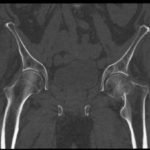

In the anteroposterior view bilateral hip x-ray, there is an evident loss of Shenton’s line on the left (red line) when compared to the normal right (white line), indicative of a fracture in the left femoral neck. This correlates with findings seen on pelvic CT, which reveals both a subcapital fracture (blue arrow) and transcervical fracture (yellow arrow). The neck of the femur is displaced superiorly relative to the head of the femur while the head of the femur remains in its anatomical position within the acetabulum.